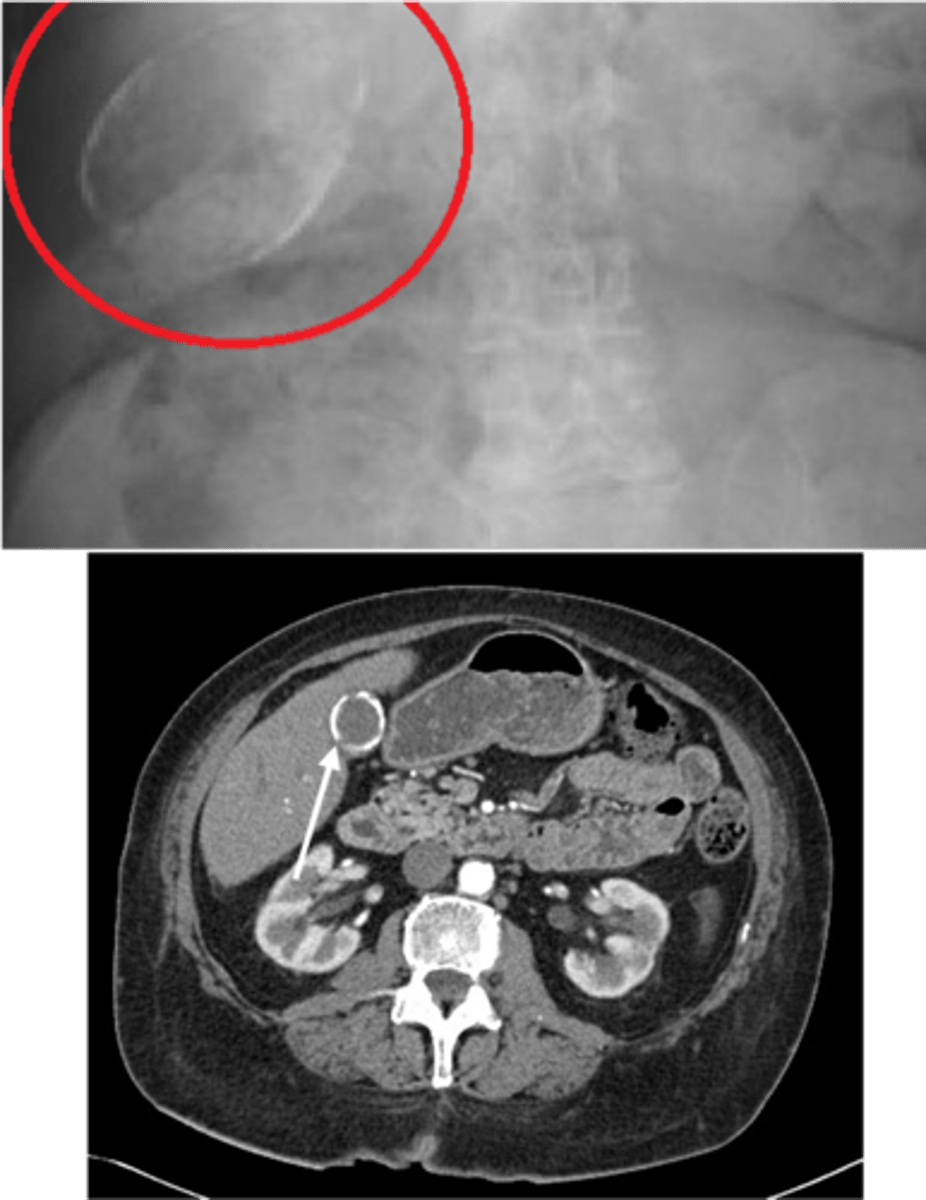

Gallstone Ileus

Define Cholelithiasis Complication:

Gallstone obstructs small bowel

-Path:

> Cholecystits w/ fistual between gallbladder & small bowel --> stone enters GI lumen ==> OBSTRUCTION at ILEOCECAL VALVE (narrowest point)

> Pneumobilia (air in biliary tree) = Fistula --> AIR from intestine fills biliary tree

-Dx: Imaging (XRAY)

> Rigler Triad = Pneumobilia, SBO, Gallstone outside gallbladder (ectopic)